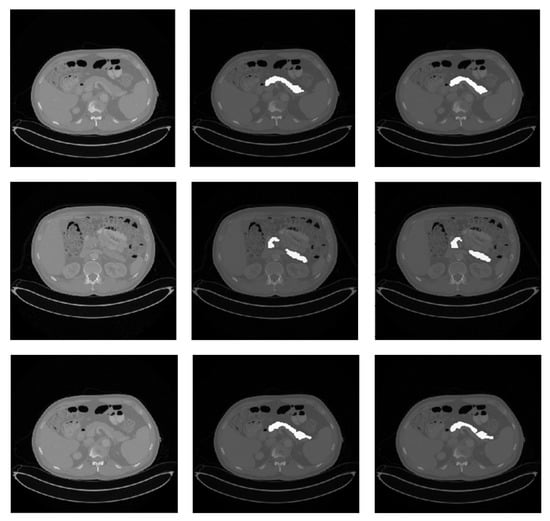

Figure 2.

Qualitative pancreas segmentation results of AX-Unet model. The images in each row arranged from left to right depicts the original image, the ground-truth segmentation, and the segmentation generated by our AX-Unet model, respectively. The segmentation results are evidently of superior quality.